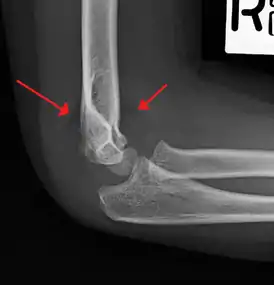

Anterior and posterior sail sign in a child who has a subtle supracondylar fracture